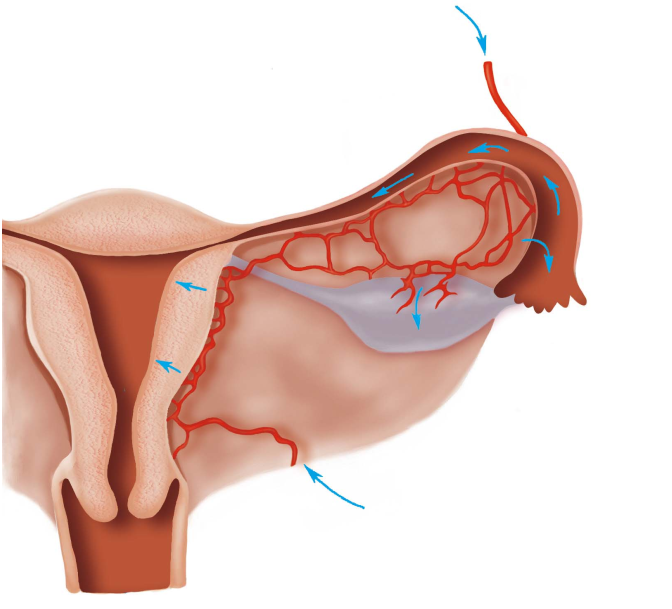

3.经血液循环传播 病原体先侵入人体的其他系统,再经血循环感染生殖器,为结核菌感染的主要途径。(图20-3)

图20-3 炎症经血行传播